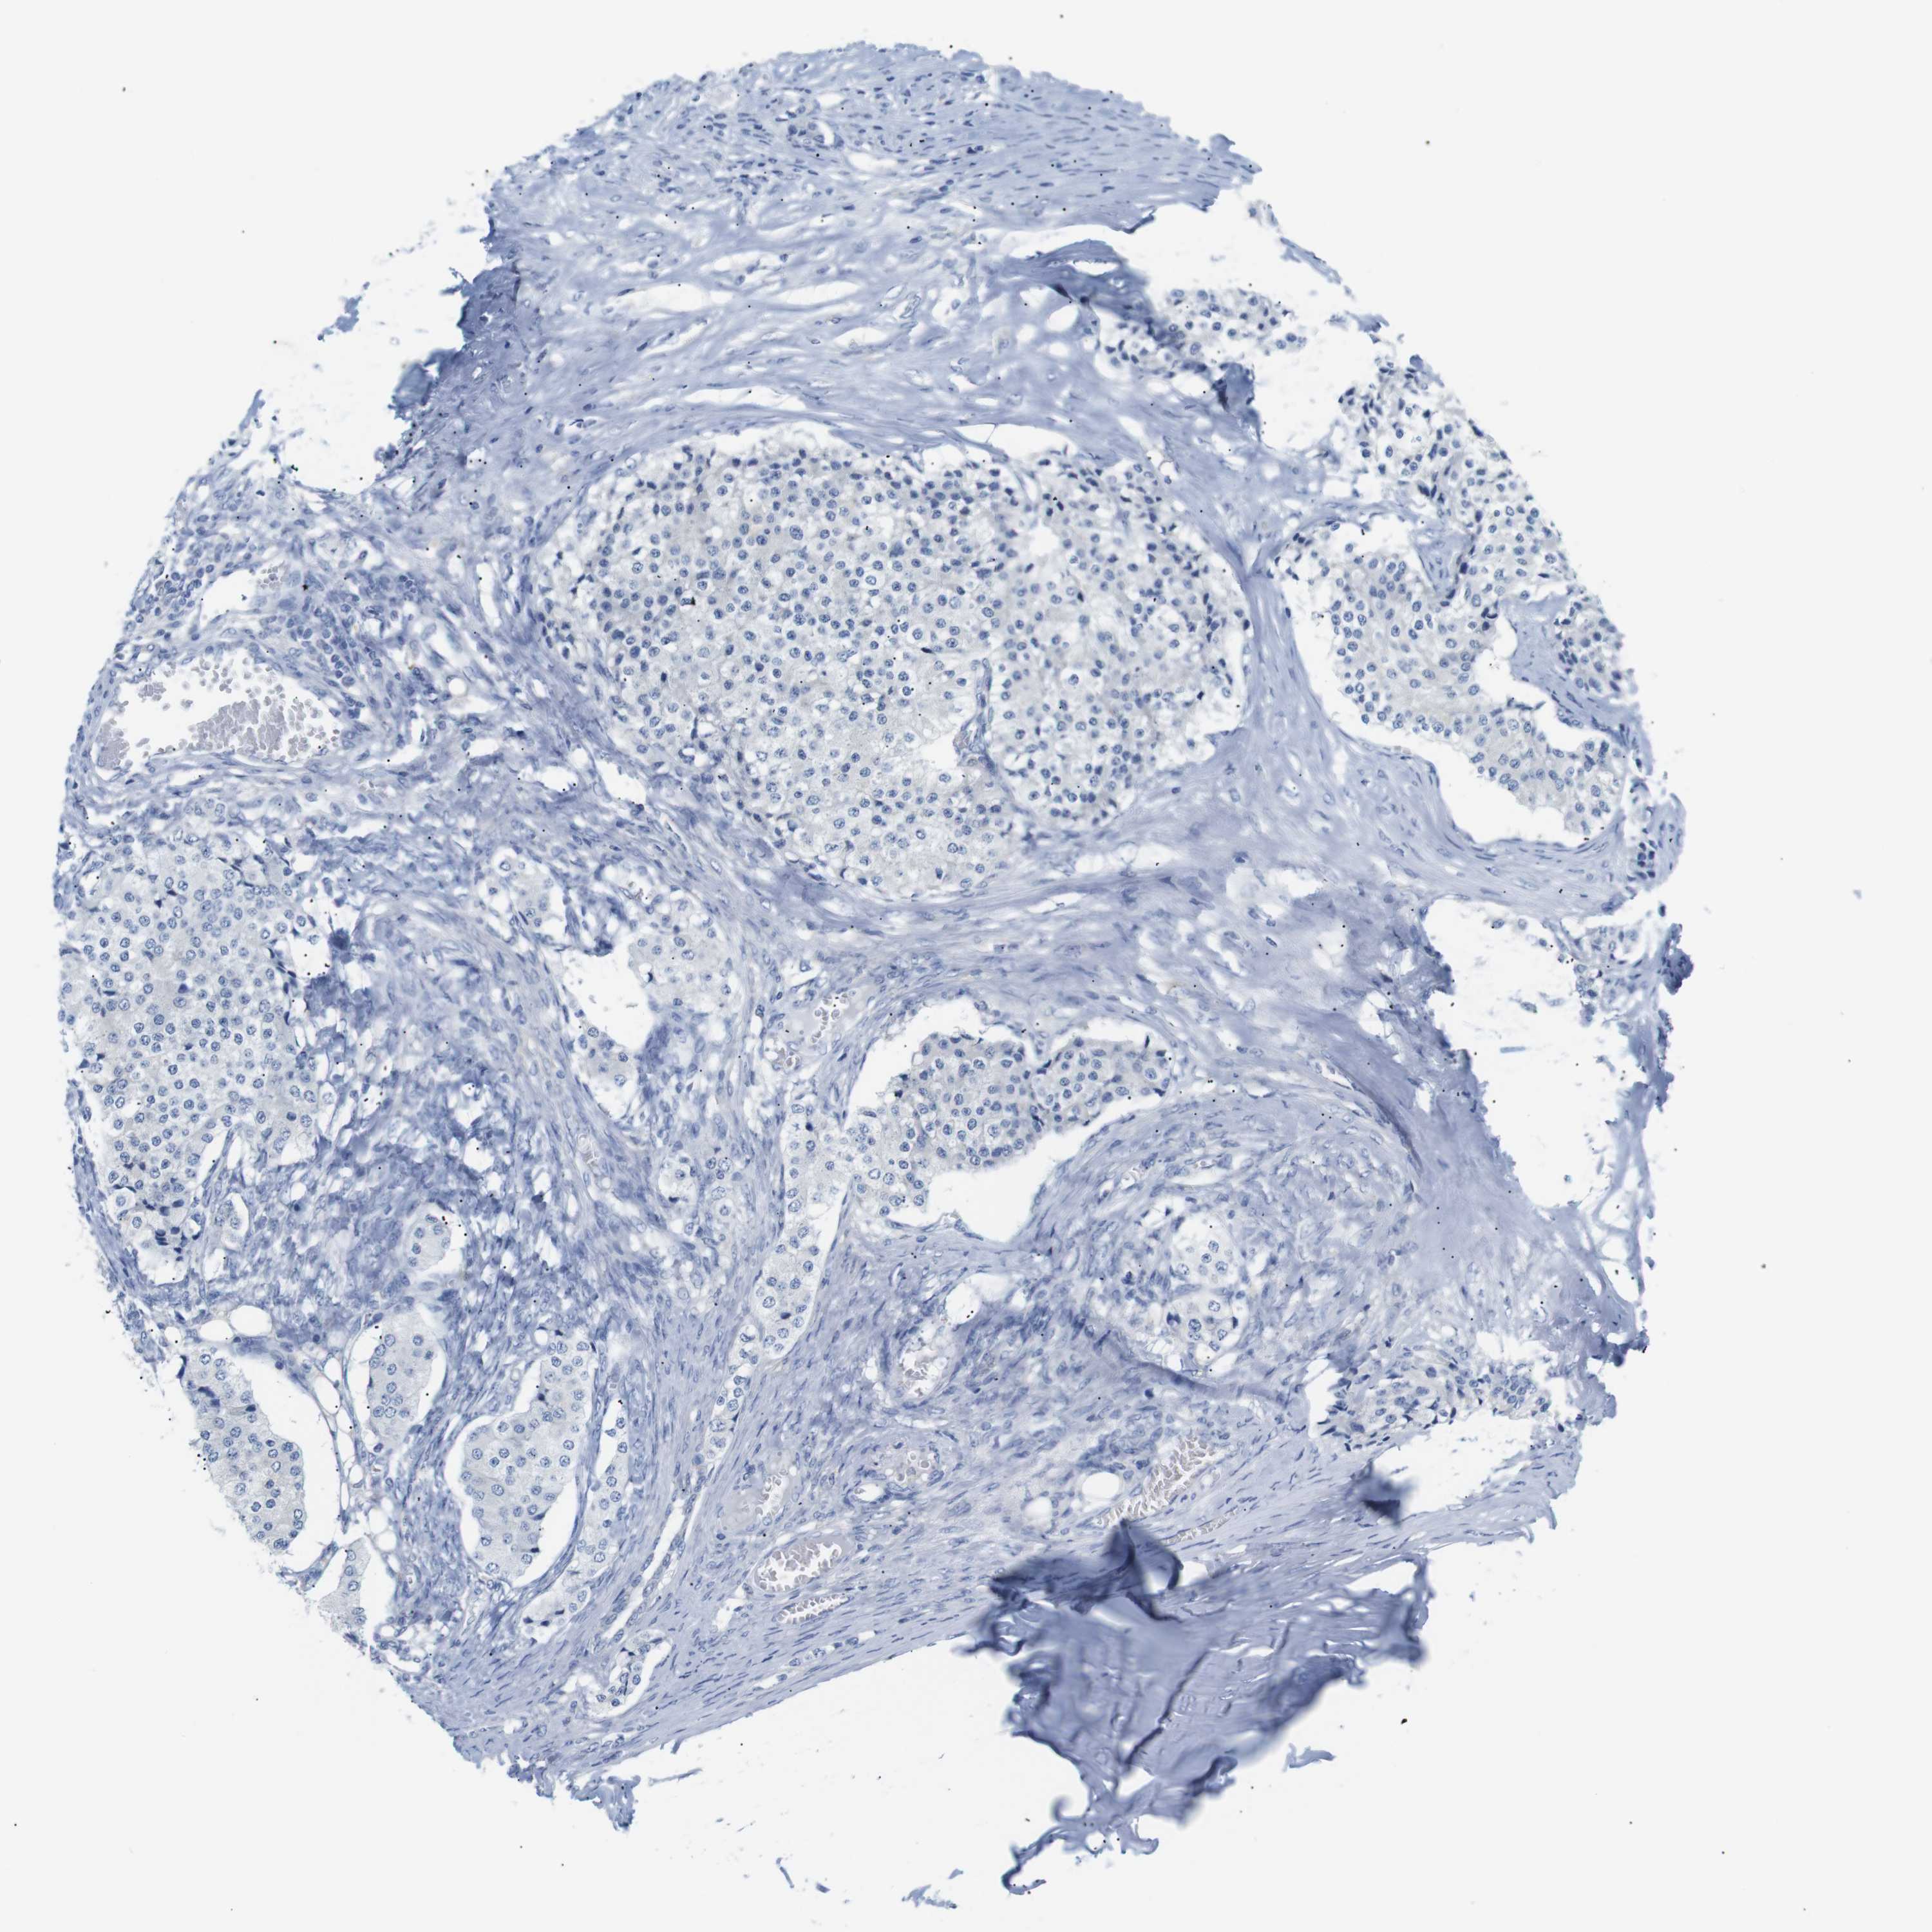

CARCINOID - Protein expressioni

A mouse-over function shows sample information and annotation data. Click on an image to view it in a full screen mode. Samples can be filtered based on level of antibody staining by selecting one or several of the following categories: high, medium, low and not detected. The assay and annotation is described here.

Antibody stainingi

Antibody staining in the annotated cell types in the current human tissue is reported as not detected, low, medium, or high, based on conventional immunohistochemistry profiling in selected tissues. This score is based on the combination of the staining intensity and fraction of stained cells.

Each image is clickable and will lead to virtual microscopy that enables deeper exploration of all samples and also displays staining intensity scores, fraction scores and subcellular localization as well as patient and tissue information for each sample.

Antibody HPA013994

Antibody HPA013995

Staining

High

Medium

Low

Not detected

Intensity

Strong

Moderate

Weak

Negative

Quantity

>75%

75%-25%

<25%

None

Location

Nuclear

Cytoplasmic/membranous

Cytoplasmic/membranous,nuclear

Carcinoid, malignant, NOS

Carcinoma, NOS